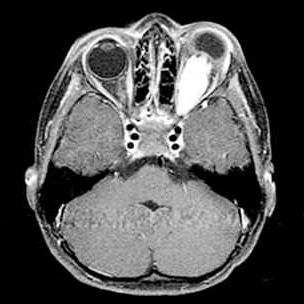

一名6岁的女童在视力检查出现问题后被转介到眼科。经检查,她的左眼视力下降(20/80)和色觉(仅限控制板)。右眼视力和色觉正常。她有一个低振幅,高频摆...

分离到视神经神经胶质瘤(ONG)是视神经胶质瘤的一个亚组,其治疗仍有争议。大多数视神经胶质瘤存在某种形式的视觉症状,这些症状由肿瘤的位置决定...

视神经胶质瘤(ONG)是较常见的原发性视神经肿瘤,通常在生命的一个十年被发现。散发性视神经胶质瘤(OPGs)通常在8岁前出现。我们的病人是ONG文献中一个没...

原发性视神经胶质瘤是较常见的良性毛细胞星形细胞瘤(WHO1级),发生在儿童时期,病程缓慢。恶性视神经胶质瘤(WHO3级至4级)发生在成年期,并遵循一个具侵...